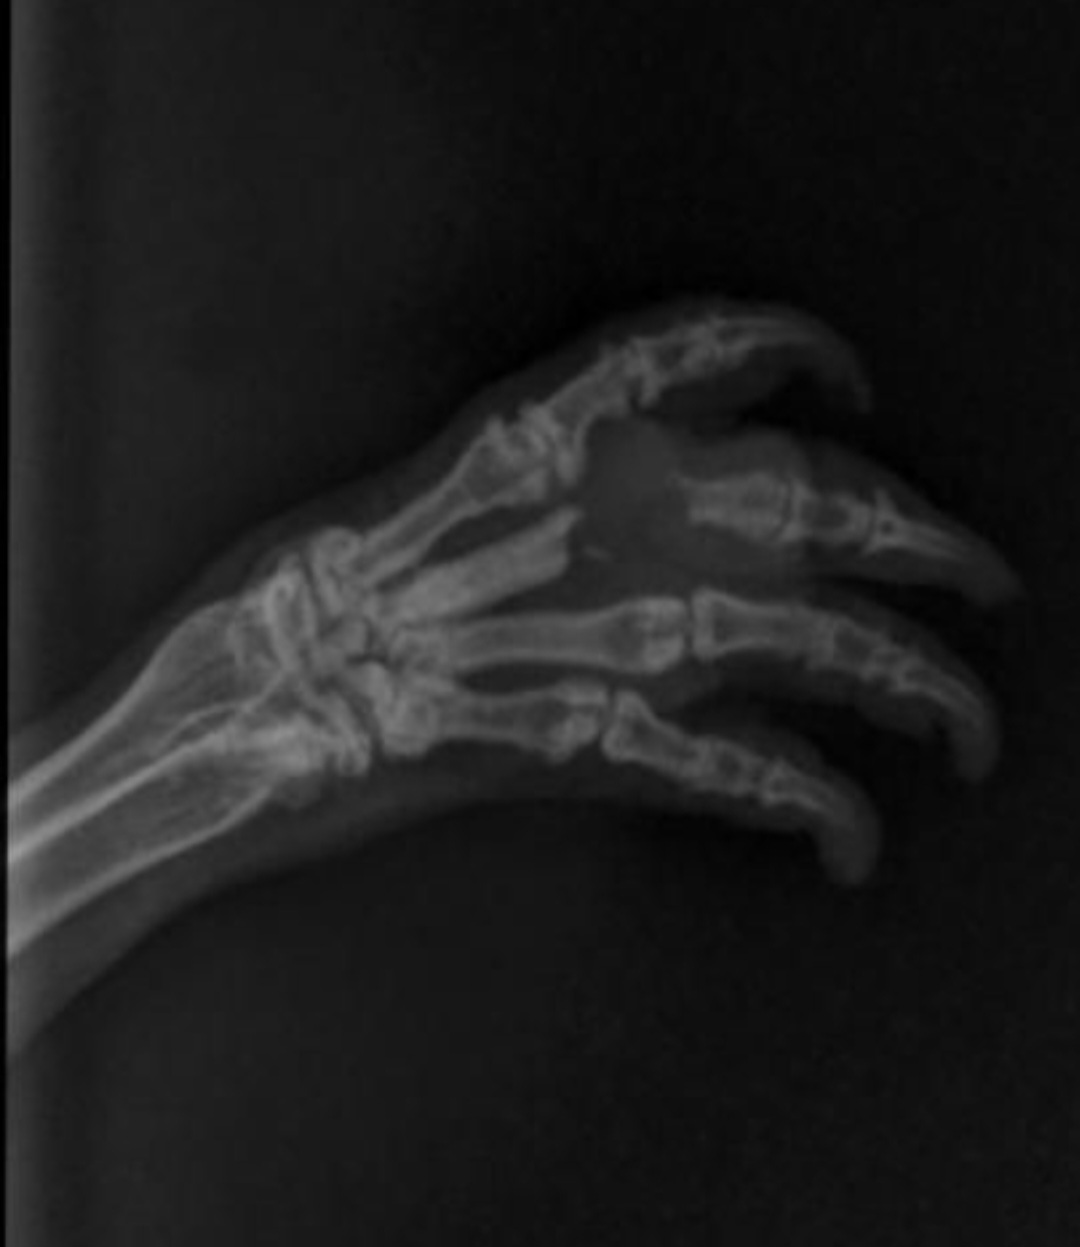

• Ich habe heute endlich das Röntgenbild erhalten und wollte es euch einmal zeigen.

Es macht mir immer noch Bauchschmerzen und ich weiß einfach nicht, was hier die beste Entscheidung ist. Ich vertraue meiner Ärztin, aber überlege trotzdem eine Zweitmeinung irgendwo online einzuholen über das Bild, aber keine Ahnung, was ich mir davon verspreche... Vermutlich möchte ich einfach hören, dass alles gut wird, was bei diesem Bild ja von vornherein ein Ding der Unmöglichkeit ist. Ein aufgelöster Knochen kann nicht mehr heile gezaubert werden.

Wir können nur hoffen, dass er sich nicht noch weiter auflöst und keine anderweitigen Probleme (Reibung/Reizung/Schmerzen usw) macht... Oder mit Risiko operieren...

• Ohne viel Ahnung von dem Thema muss ich mal etwas fragen:

Es geht vermutlich um die von oben gesehene 2. Zehe und dort um das Grundgelenk?

Dort sehe ich etwas dunkles, das aber wirkt als würde es über den Knochen liegen. Zudem dehnt sich das bis über die erste Zehe aus. Das würde doch nicht passen?

Oder meine ich die falsche Stelle und wenn ja, um welche geht es dann?

• Oh, das sieht ja echt nicht gut aus. Da ist ja durch die Zyste schon das komplette Gelenk und jeweils die Hälfte der angrenzenden Knochen verschwunden. Außerdem scheint auch der Knochen der angrenzenden Zehe angegriffen zu sein.

Ich als Laie finde das große Ausmaß des Ganzen schon erschreckend.

Hat der Tierarzt gesagt, ob das weiter fortschreitend ist?

Hat man ausgeschlossen, dass es sich um Knochenkrebs handelt?

• Das sieht wirklich erschreckend aus. Könnte das vielleicht auch Osteomyelitis oder Ostitis sein, also eine Entzündung des Knochenmarks oder Knochen? Die Weichteilschwellung und das vorangegangene Trauma/Biss könnten dafür sprechen. Für Knochenkrebs sehen mir die Endstellen irgendwie zu glatt aus. Das hätte ich mir bei Krebs eher ausgefranst vorgestellt.

• Ja genau, es betrifft die zweite Zehe von links (oben), da wo der Knochen "weg" ist. Das an der ganz linken Zehe diese eine "Ecke" betroffen ist, hab ich vorher tatsächlich gar nicht so wahrgenommen. Keine Ahnung ob da jetzt wirklich etwas "drüber" liegt, was den Knochen versteckt, oder ob dieser ebenfalls betroffen ist.

Muss ich die Ärztin nochmal zu fragen.

Knochenkrebs hatte die Ärztin als Möglichkeit angesprochen.

Eine Entzündung als Ursache der Knochenauflösung ist ebenfalls möglich und fände ich im zeitlichen Zusammenhang plausibler. Vor dem Biss gab es keine Probleme, erst danach.

Es wurden inzwischen 3 Röntgenbilder der Pfote gemacht mit wachsender Verschlechterung.

Bild 1 am Tag nach dem Biss: unauffällig

Bild 2 eine Woche nach dem Biss: in der Zehe war die vermeintliche Knochenzyste zu sehen, da wo jetzt kein Knochen mehr ist

Bild 3 dreieinhalb Wochen nach dem Biss: sieh oben

Bisher wurde er die ganze Zeit gegen Entzündung behandelt mit Spülen, Bädern, Salben, Metacam und zwei ABs (Antibiogramm ohne Befund).

• Keine Ahnung ob da jetzt wirklich etwas "drüber" liegt, was den Knochen versteckt,

Leider kann da nichts drüber liegen. Alles was im Röntgen dunkel ist, ist ohne viel Dichte wie z.B. Luft. Wenn etwas drüber liegen würde, müsste es mehr Dichte als der Knochen haben und wäre somit weiß.

Danke für den Hinweis, dann wäre das mit dem "Überdecken" ja ausgeschlossen und der Knochen ist tatsächlich weg und die ganz linke Zehe vermutlich auch (zumindest leicht) irgendwie betroffen.

Womöglich war die vermeintliche Knochenzyste bereits der Beginn der Auflösung? Ich weiß es nicht... Alles echt großer Mist ;(

Zu der Aufnahme: Für mich sieht es immer noch so aus, als wäre es über dem Knochen. Ich weiß nicht, ob es Gewebe oder Eiteransammlungen o.ä. gibt, die so eine Darstellung bewirken können. Ich kann mich mit meiner Sicht natürlich irren, aber es sieht auch leicht anders aus als das übrige Gewebe um die Knochen herum - und das müsste man ja sehen, wenn Teile der Knochen fehlen würden.

• Wenn Knochen abgebaut wird, wandelt ihn der Körper in anderes Gewebe um. Vielleicht ist es das, was du siehst - die dunklere Stelle wo vorher der Knochen war. Also ich denke auch, dass da nichts darüber liegt. Das erscheint nur so, wenn wir es uns räumlich vorstellen.

• Kontrolltermin ist durch. Das Röntgenbild von Johnnys Pfote ist unverändert zu letzter Woche. Keine weitere Veränderungen an den Knochen. Die Zehe nur noch minimal dick. Die Wunde komplett geschlossen.

Da er vom Verhalten her auch normal drauf ist, probieren wir es jetzt so weiter. Sollte eine Verschlechterung eintreten, müsste man weiterschauen bis hin zur Amputation. Wir hoffen aber, dass es so gut geht.